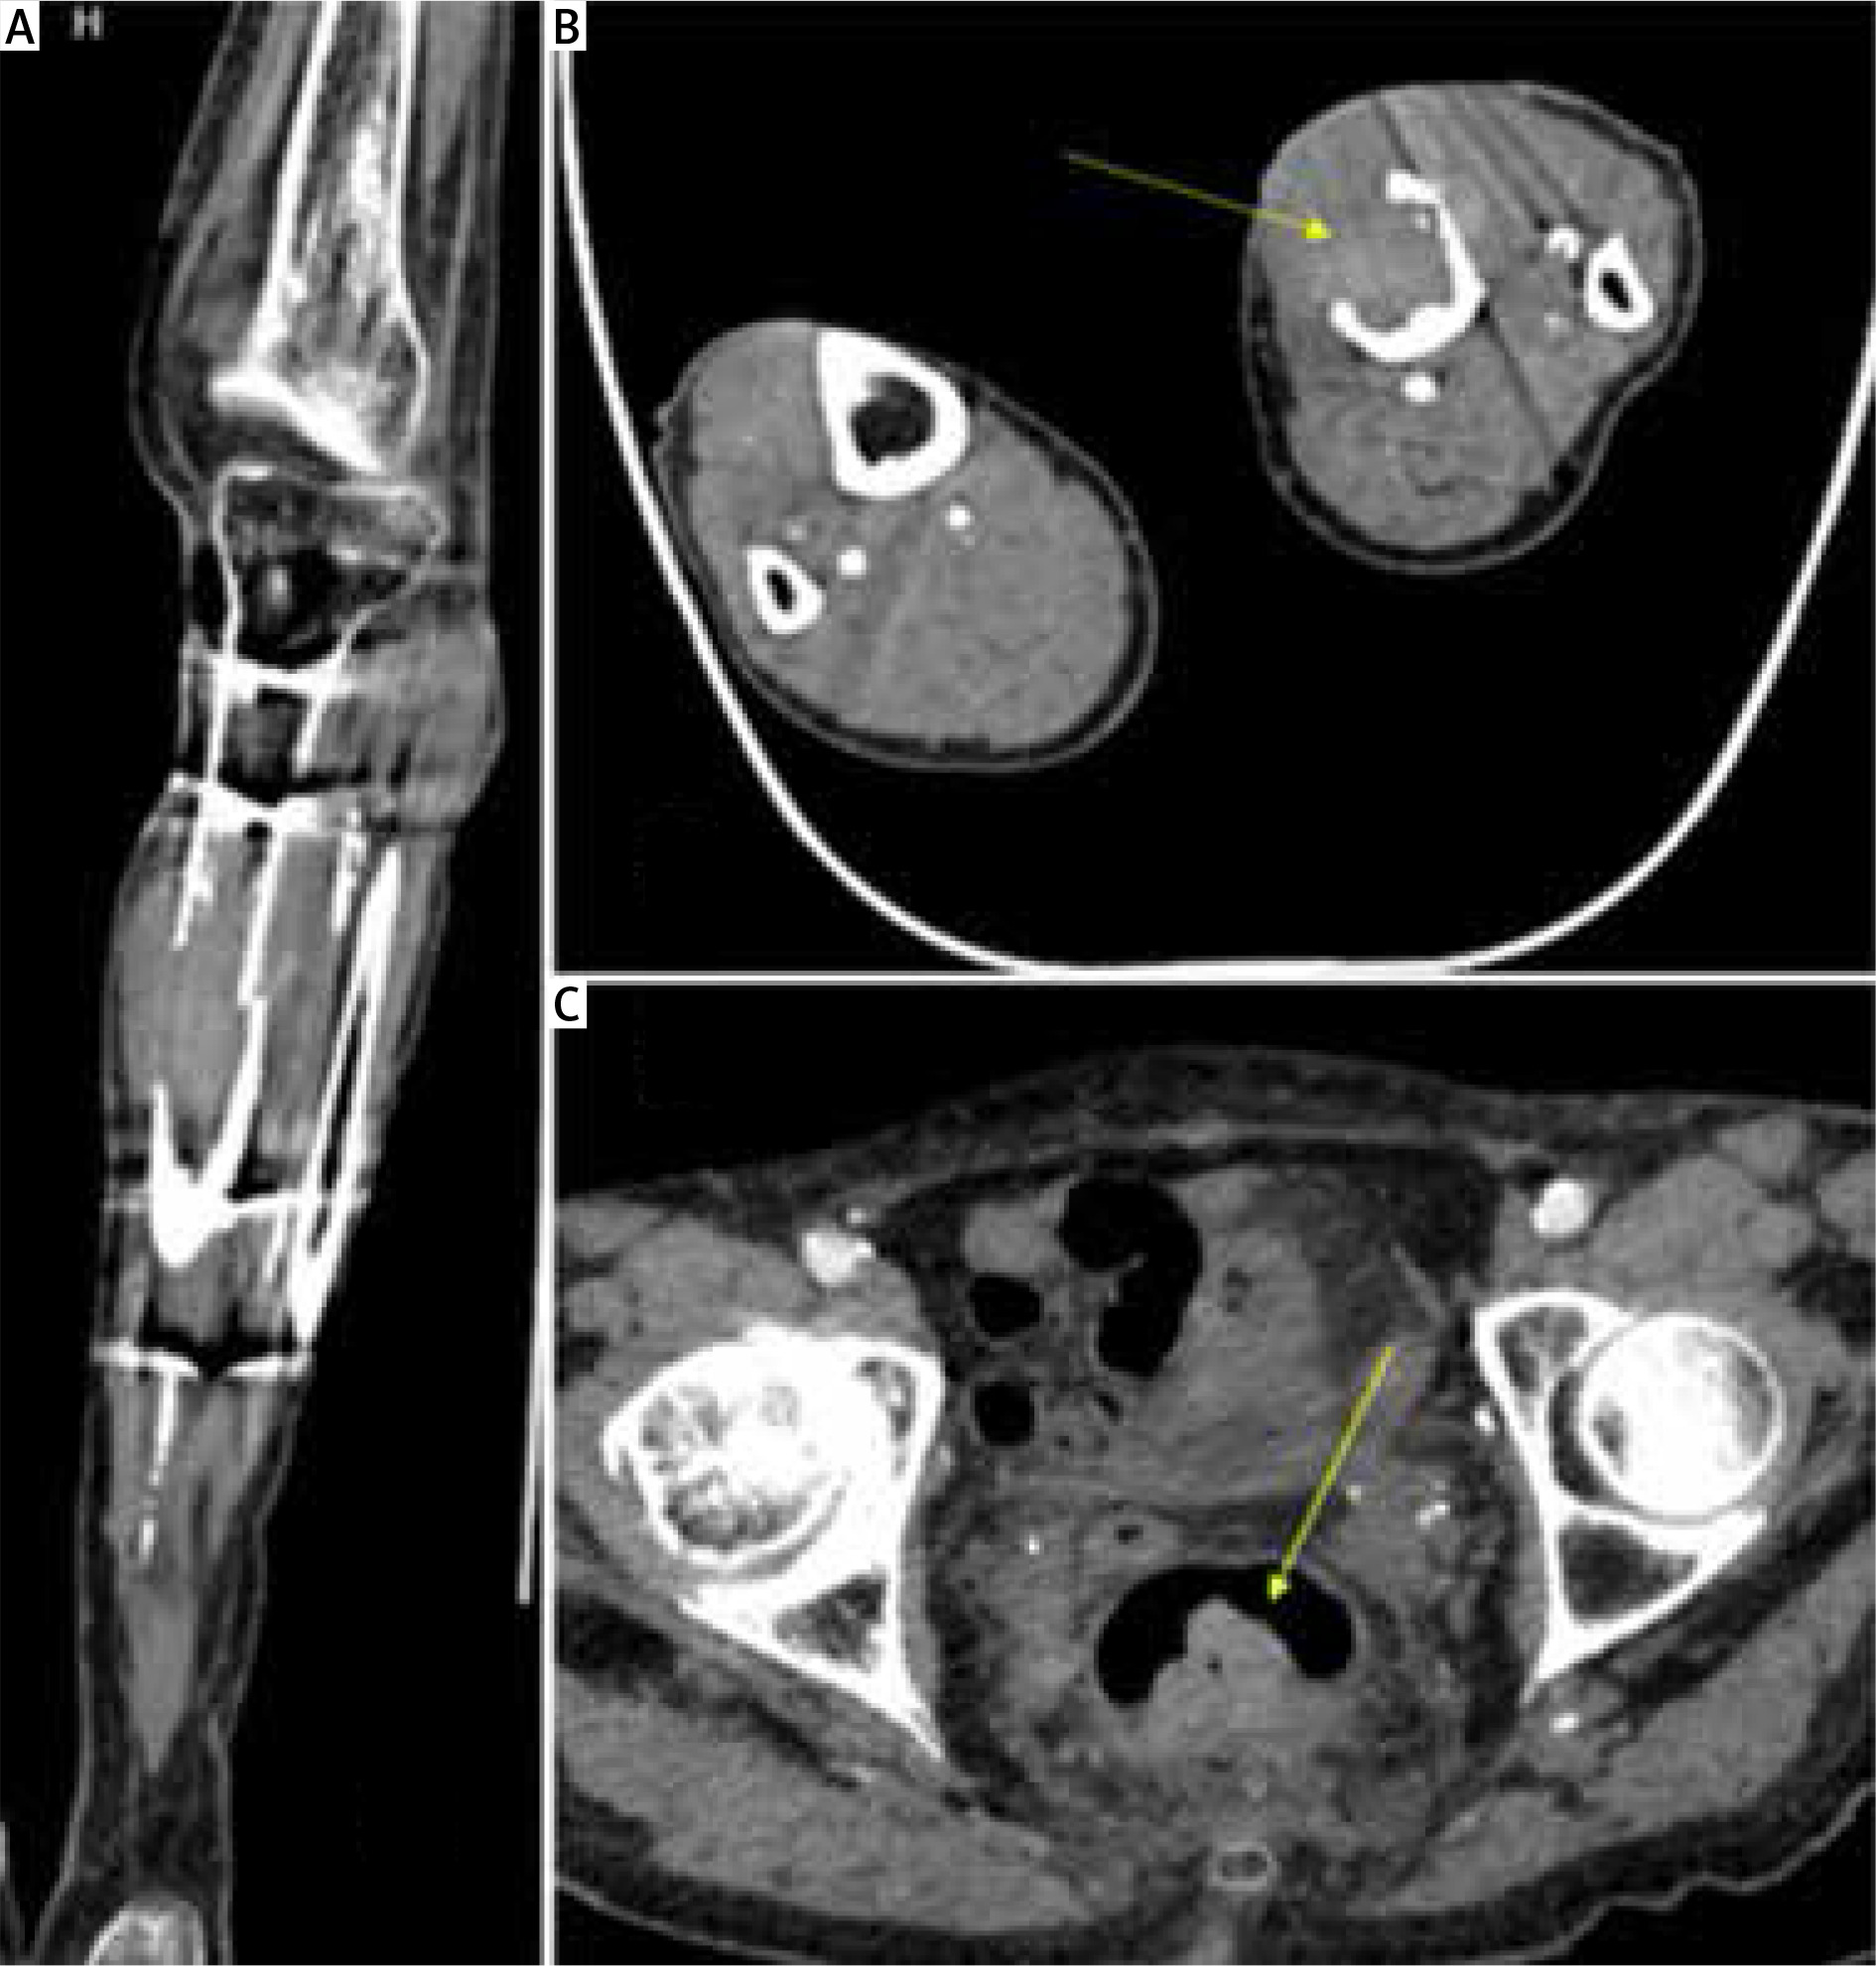

Figure 4

A – Coronal plane of MSCT – osteolytic tibial lesion, B – Axial plane of MSCT – osteolytic lesion in the diaphysis of the left tibia covering almost all the diameter of the bone in this site, C – Axial plane of abdominal MSCT showing rectal mass